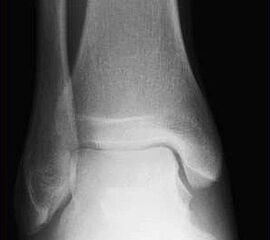

Neben der klinischen Untersuchung (Schwellung, Druck- und Klopfschmerz, Berührungsempfindlichkeit) sind Röntgenuntersuchungen obligat, obwohl sie gerade in den ersten Wochen der Erkrankung kein Korrelat bieten, aber zur differentialdiagnostischen Abgrenzung dienen. Im weiteren Krankheitsverlauf  zeigt sich nach Wochen und Monaten im Röntgen und im CT eine Osteopenie  in der betroffenen Region 8119 (Abb. 4 und 5)